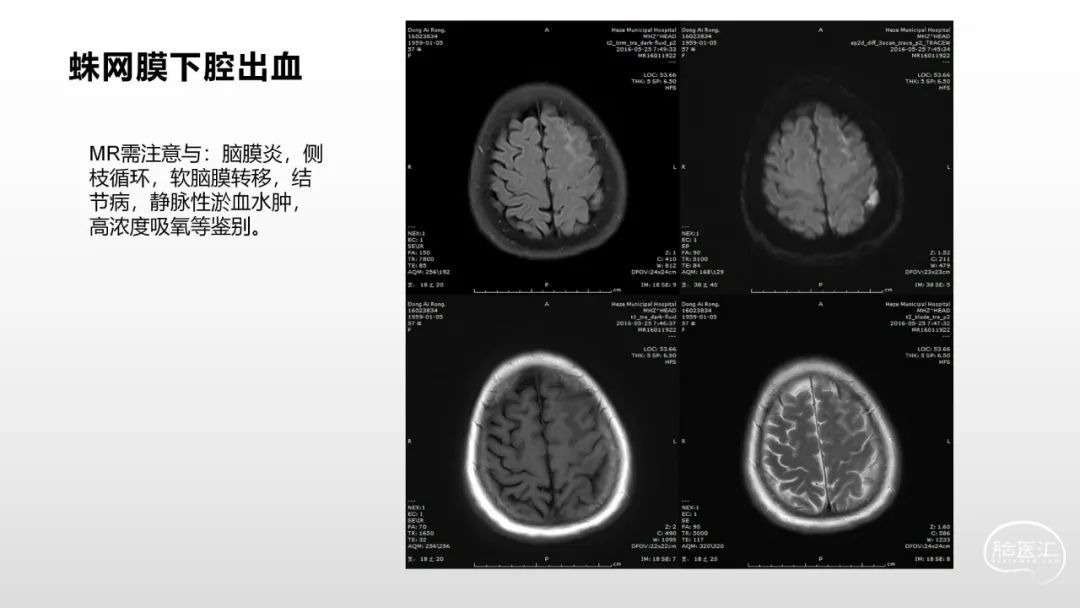

颅脑影像诊断基础知识讲座:《脑血管病》之出血、血管畸形、动脉炎及神经卡压